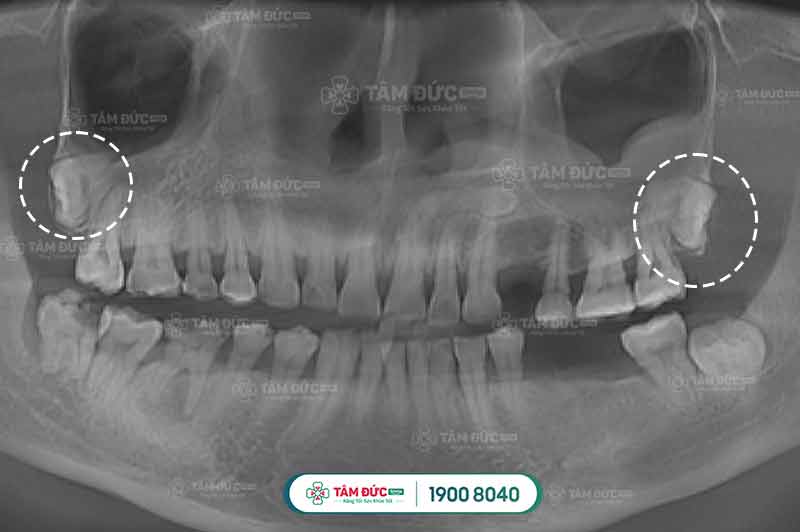

Trường hợp răng khôn mọc lệch, mọc ngầm

1.2. Răng khôn mọc lệch, mọc ngầm

Đối với những chiếc răng khôn mọc lệch lạc, mọc ngầm này, dù răng Quý khách có bệnh lý như thế nào rặng hay nhẹ cũng sẽ được bác sĩ chỉ định nhổ bỏ ngay vì nó ảnh hưởng rất lớn đến sức khỏe người bệnh.